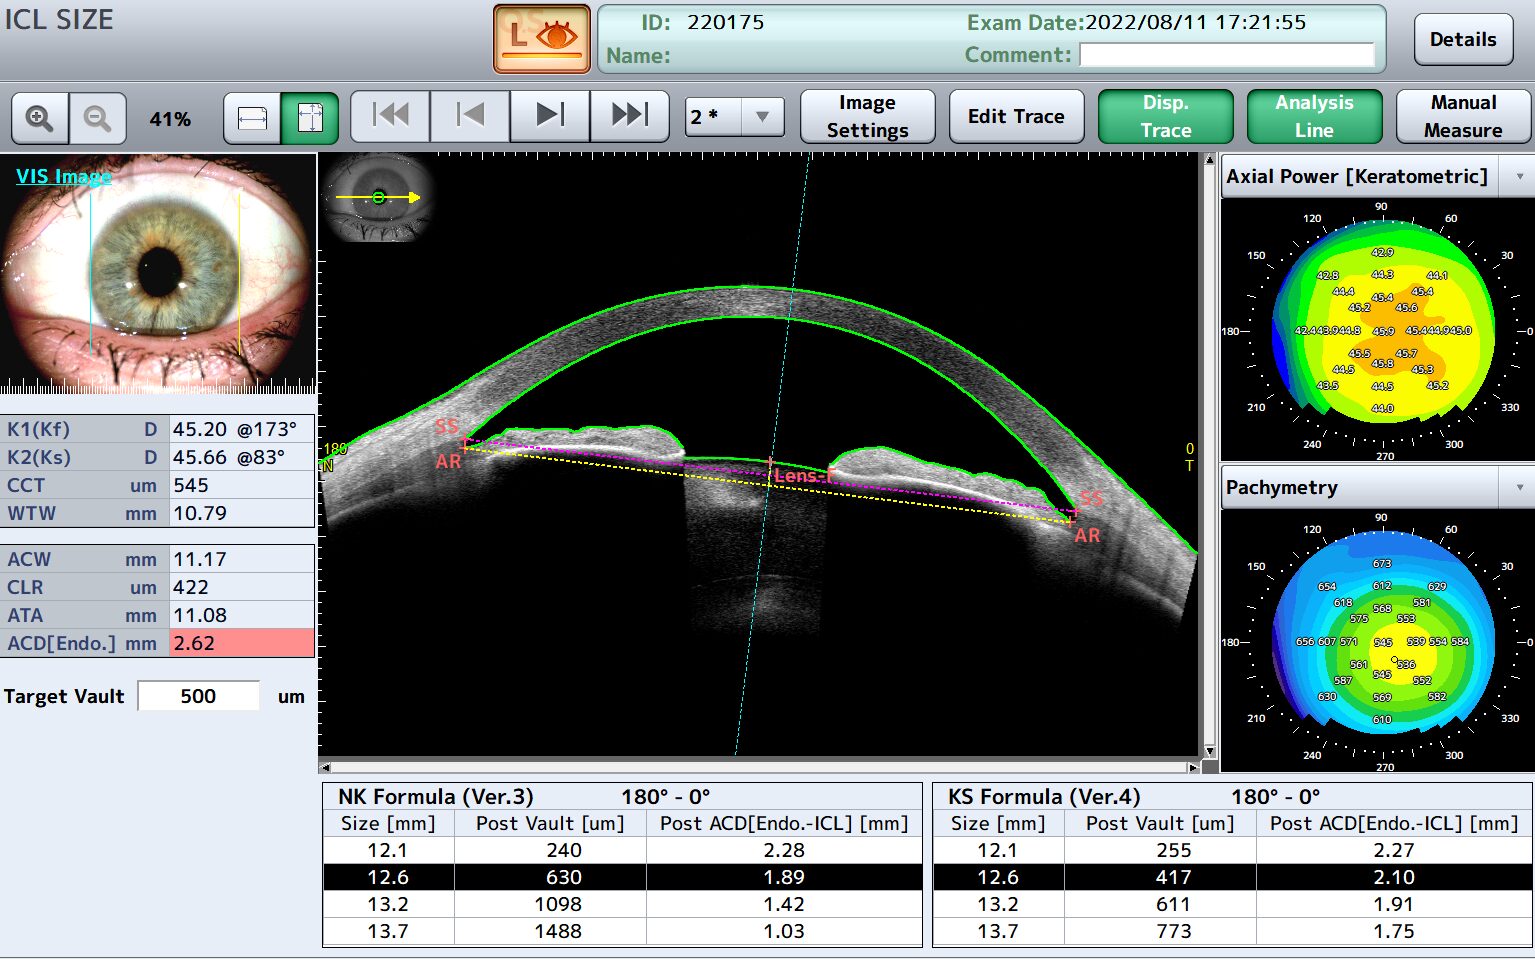

- ICL